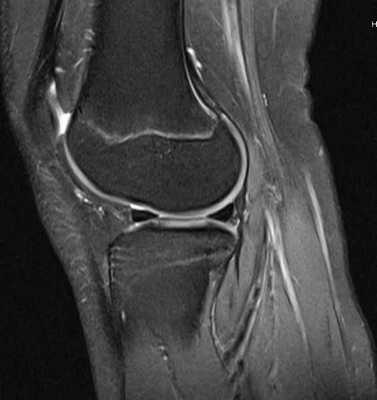

МРТ коленного сустава. МРТ в отличии от рентгенографии представляет детальную визуализацию мягких тканей. На МР-томограмме в боковой плоскости опредляются передняя и задняя крестообразные связки (стрелки)

МРТ коленного сустава.В норме на МР-томограмме коленного сустава хрящ (яркий) покрывающий суставную поверхность имеет равномерную толщину, суставная поверхность имеет ровную форму, возможно минимальное количество жидкости, мениск имеет гипоинтенсивный МР-сигнал. У молодых людей имеется гипернтенсивный сигнал в метаэпифизе — зона роста (яркий МР-сигнал).